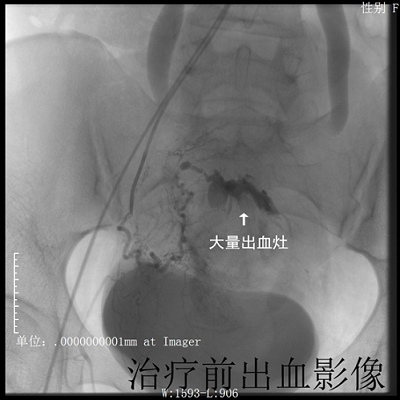

首例急诊产后子宫大出血患者在我院介入手术成功

近日,我院放射科、妇产科携手合作,采用介入技术,成功地为一名27岁的产后大出血患者实施了子宫动脉栓塞手术。此手术的成功实施在我院尚属首例。

患者陈某于外院行剖宫产术后大出血,急诊转入我院治疗。来院时患者神志萎靡、精神不振,检查示:血红蛋白55g/l且出血不止,情况危急。给予抗感染、输血及子宫收缩等对症治疗,未见明显好转。以往这种情况,为了挽救患者生命,只有切除患者的子宫。可患者年仅27岁,子宫切除将大大影响其今后的生活质量。妇产科唐华主任医师、王健主治医师立即与放射科联系,请陈应付副主任医师和赵蔚副主任医师应用介入手术解决这一难题,手术取得成功,患者子宫得以保住。